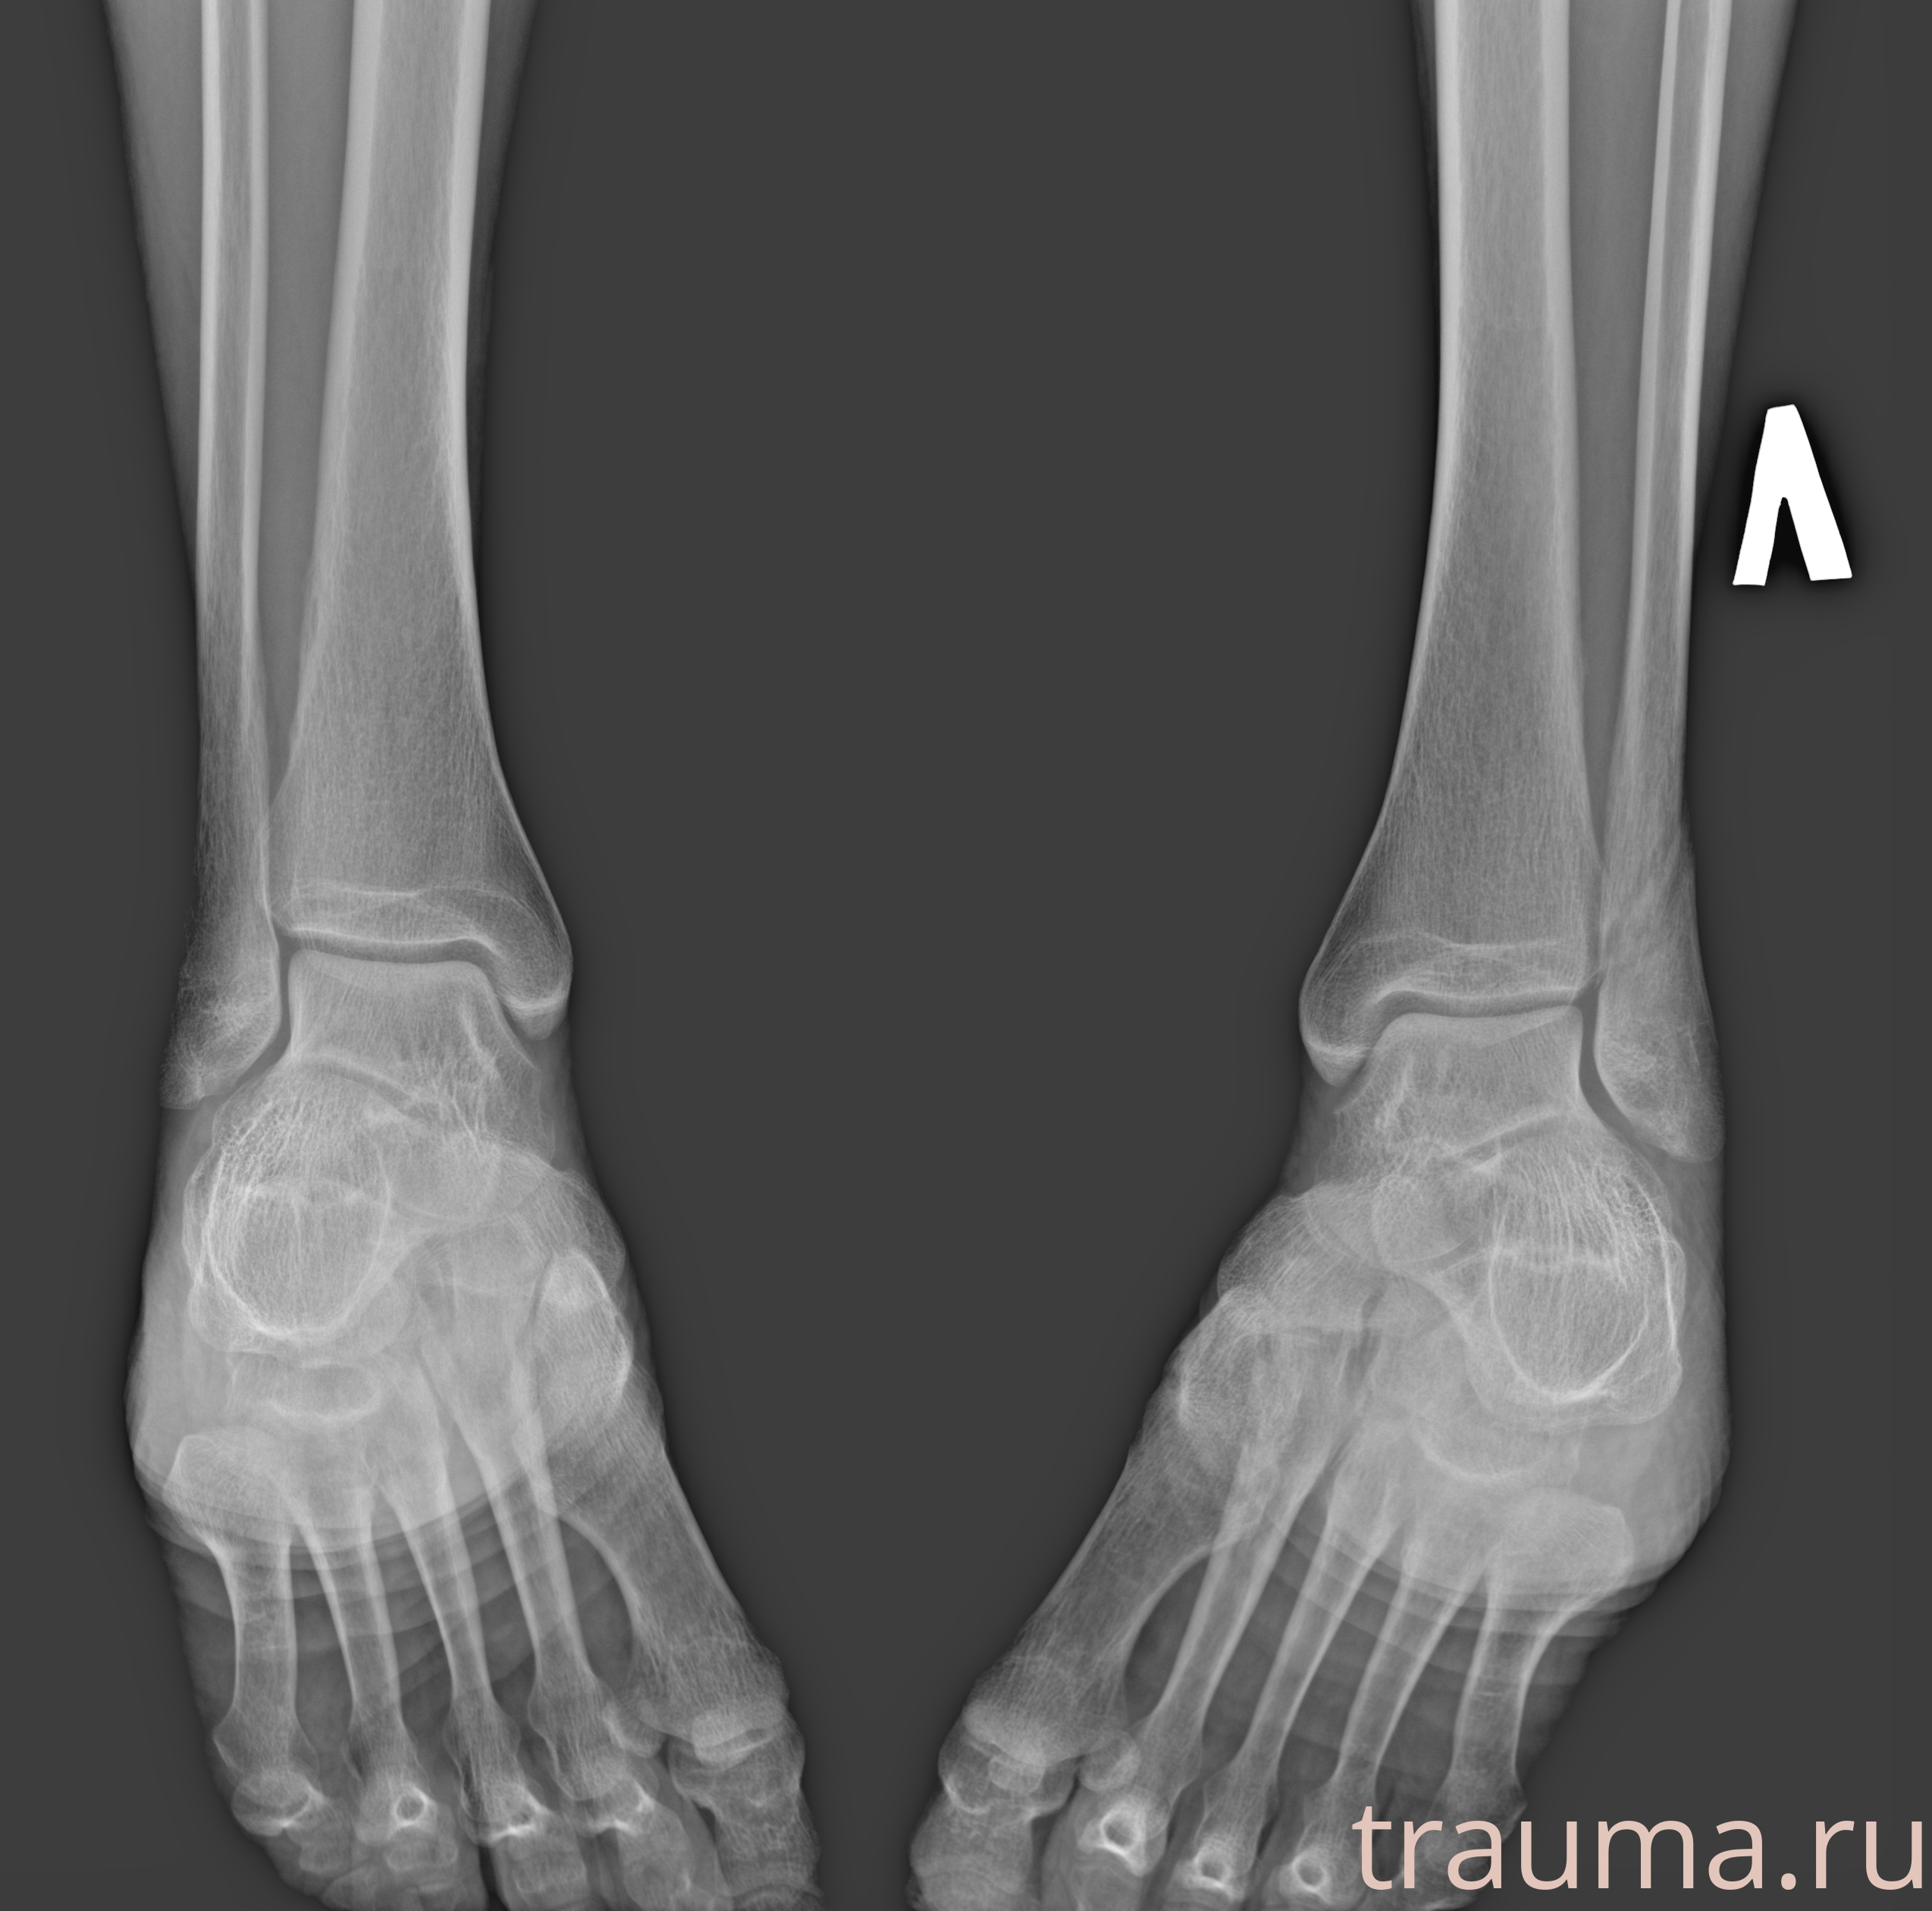

Рентгенограммы

Рентген на дому: по вашему адресу приезжает врач-рентгенолог, травматолог-ортопед с мобильным рентгеновским аппаратом, проводит диагностику травмы или заболевания, делает необходимые рентгенограммы, дает рекомендации по дальнейшему лечению. Получить качественные снимки в домашних условиях возможно благодаря уникальной методике, разработанной МосРентген Центром для института  Склифосовского

Яркость: 1   Контраст: 1   Инвертировать: 0 Увеличение: 1

Перетаскивайте мышь вверх/вниз для контраста, влево/право для яркости. Прокрутка колесом изменяет масштаб. Нажмите Сбросить для возврата к исходному изображению. При увеличении держите мышь в той области, которую хотите рассмотреть.